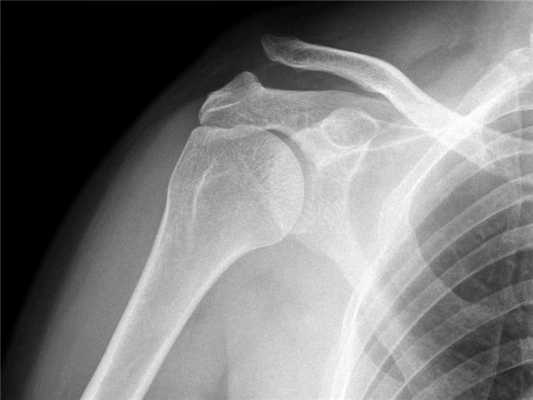

- Первичное рентгенологическое исследование должно включать рентгенограммы в передне-задней проекции, проекции по Grashey, боковой Y-лопаточной проекции и подмышечной проекции. Эти рентгенограммы позволят оценить состояние плечелопаточного и АК суставов

- Проекция по Zanca информативна для оценки состояния АКС и представляет собой передне-заднюю проекцию с краниальным наклоном луча до 10-15° (рис. 2) и снижением напряжения на трубке до 50% (Zanca, 1971). Признаками артрита АКС являются подвывих, склероз, сужение суставной щели, формирование субхондральных кист и остеофитов (рис. 3)